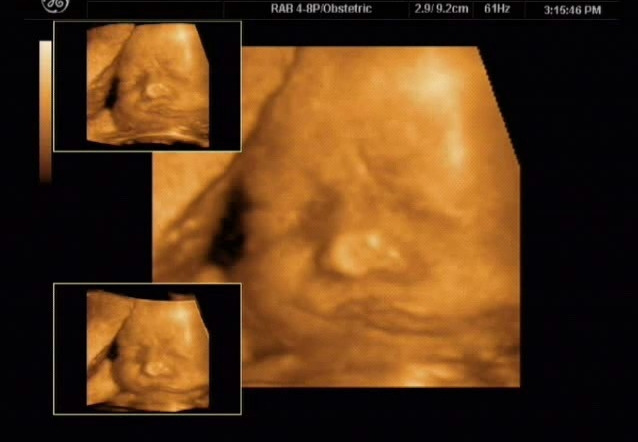

출산교육자료 중에 제일은 두 장의 경태 사진이다. 커리큘럼 중 태교를 설명할 때 등장한다. 첫 번째 사진은 경태가 미간을 찌푸리고 입이 뿌루퉁한 모습이고 그로부터 오분이 지난 후 사진은 미간 주름이 펴지고 입꼬리가 올라가 마치 헤벌 적 웃는 모습이다. 뱃속의 아기가 오분의 간격을 두고 상반된 얼굴 표정을 보이는 것이 하도 신기하다며 경태 엄마는 그 사진을 내게 가지고 왔다. 경태 엄마의 자초지종을 듣고서는 소름이 돋았다.

경태 엄마는 아기의 입체사진을 찍으러 병원을 방문했고 한참을 기다린 후에야 대기명단에 없다는 걸 알았다. 화를 냈고 기존 대기자들에 앞서 초음파를 하게 되었다. 화가 나서 가슴이 두근거렸고 영 기분이 풀리지 않은 채 초음파를 보기 시작했다. 배에 젤리를 바르고 초음파 프루브가 동그란 배를 원 그리 듯 문지르자 경태가 보이기 시작했다. 잠시 아기를 살피던 소노 그래퍼가 "어머! 경태가 인상을 쓰고 있어요 경태 어머니! 엄마가 화를 내니 아기도 화를 내고 있잖아요~보세요!" 경태의 얼굴을 클로즈업했다. 정말 경태가 오만상을 쓰고 화가 난 얼굴을 하고 있었다. 경태 엄마는 섬찟하기도 했지만 한편 미안하다는 생각도 들었다. 얼른 정신을 차리고 진심으로 미안하다는 말을 했다. 계속해서 계속해서 그렇게 말했다. 사랑한다고도 했다. 소노 그래퍼가 경태의 다른 부분을 열심히 확인하는 시간에도 아기를 생각하며 용서를 구했다. 다시 얼굴 쪽으로 프루브를 대었다."어머나! 경태가 웃고 있어요!" 이게 웬일인가! 정말로 경태가 웃고 있었다. 찡그린 이마는 펴져 있었고 입꼬리는 올려져 있었다. 신기한 두장의 사진으로 태내 아기는 엄마의 감정에 휘둘린다는 것을, 나아가 임신한 엄마의 표정이 아기의 표정과 같다는 확신이 들었다. 경태 엄마는 남은 임신기간 동안 화를 내지 않으려 노력했다. 내 손에 올려진 경태는 울지 않고 바로 고른 숨을 쉬었으며 눈을 뜨고 엄마를 바라보았다.